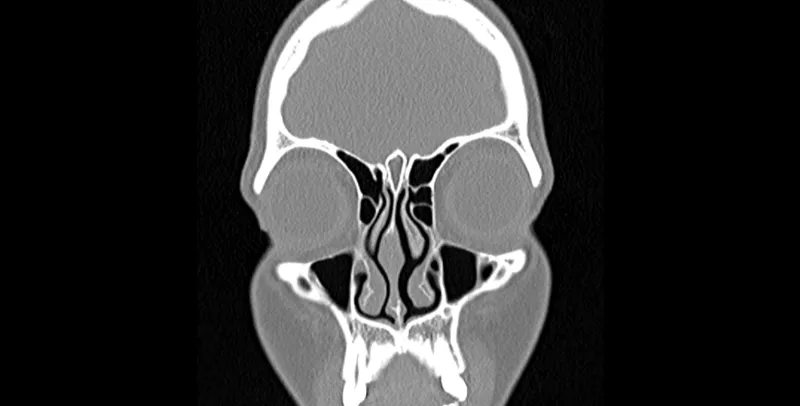

- Imaging (CT scan preferred over X-ray):

- Indicated for suspected orbital or intracranial complications.

- Evaluation of chronic or recurrent sinusitis unresponsive to medical therapy.

- Pre-operative planning for functional endoscopic sinus surgery (FESS).

⭐ CT scan is the gold standard imaging modality for assessing complicated or chronic pediatric sinusitis and prior to surgical intervention.